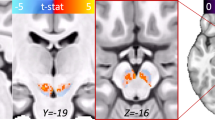

The development of molecular probes that allow in vivo imaging of neural signaling processes with high temporal and spatial resolution remains challenging. Here we applied directed evolution techniques to create magnetic resonance imaging (MRI) contrast agents sensitive to the neurotransmitter dopamine. The sensors were derived from the heme domain of the bacterial cytochrome P450-BM3 (BM3h). Ligand binding to a site near BM3h's paramagnetic heme iron led to a drop in MRI signal enhancement and a shift in optical absorbance. Using an absorbance-based screen, we evolved the specificity of BM3h away from its natural ligand and toward dopamine, producing sensors with dissociation constants for dopamine of 3.3–8.9 μM. These molecules were used to image depolarization-triggered neurotransmitter release from PC12 cells and in the brains of live animals. Our results demonstrate the feasibility of molecular-level functional MRI using neural activity–dependent sensors, and our protein engineering approach can be generalized to create probes for other targets.